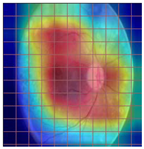

| Original Image | VGG16 | ResNet-18 | DenseNet-121 |

|---|---|---|---|

![]() | ![]() | ![]() | ![]() |

| (a) | |||

| (b) | |||

| (c) | |||

| (d) | |||

| Model | Conformity with Normal Retinal Photos | Conformity with Abnormal Retinal Photos | Average Conformity |

| VGG16 | 0.2000 | 0.2414 | 0.2207 |

| ResNet-18 | 0.0294 | 0.0645 | 0.0469 |

| DenseNet-121 | 0.0385 | 0.0286 | 0.0336 |